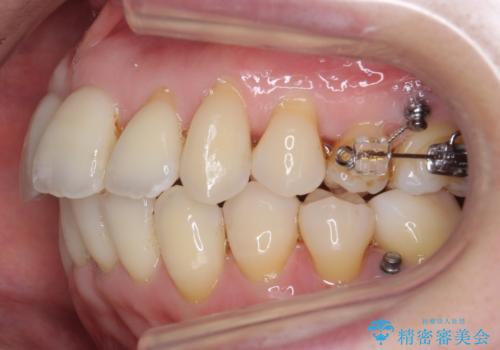

左下の奥歯が内側に倒れこみ、左上の奥歯は向きが悪くすれ違っていました。

ワイヤー矯正とマウスピース矯正を併用し、左上の位置が悪い歯は抜歯し、左上の親知らずを手前に移動させました。

左上下のかみ合わせが悪く、歯石も多かったため、歯周病の治療も併せて行いました。

難易度の高い部分はワイヤー部分矯正を行うなどして対応し、見える部分はマウスピース矯正を併用する工夫を行いました。